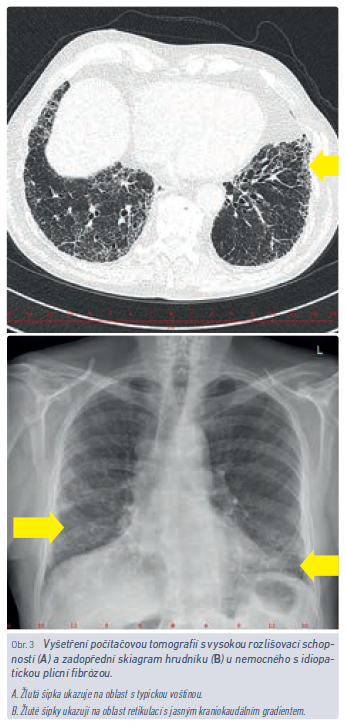

Nemocní s IPF jsou obvykle starší než pacienti se sarkoidózou a EAA. Je pravda, že typickým pacientem s IPF je bývalý kuřák, muž ve věku kolem 70 let, nejedná se ale o podmínku sine qua non (obr. 3). Polymorbidita není výjimkou, dosti typickým pro chorobu však bývá poslechový nález krepitu nad plicními bázemi.14 Někteří pacienti mají paličkovité prsty, které obvykle sami jako znak možného onemocnění nehodnotí, lékař by ale jejich přítomnost přehlédnout neměl. I když subjektivní obtíže v počátku onemocnění bývají pacientem bagatelizovány a přičítány věku, přidruženým onemocněním či nadváze a dekondici, časné stanovení diagnózy, především však časné zahájení antifibrotické léčby dramaticky mění prognózu těchto nemocných. Krepitus je velmi senzitivním ukazatelem fibrotického plicního postižení, proto i v době moderních technologií hraje fyzikální vyšetření pacienta nezbytnou úlohu a v rámci preventivních prohlídek by nemělo být opomíjeno.